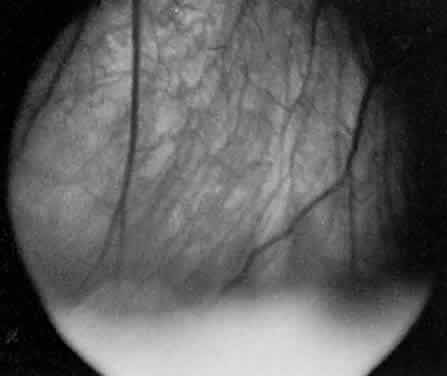

In pars planitis, the inflammatory signs are greatest in the vitreous cavity. The vitreous gel is syneretic and shows varying amount of fibrin, cells, and strands. The hallmark of pars planitis is the presence of exudates in the inferior vitreous base (Fig. 1). In early stages these exudates may appear as discontinuous yellow-white clumps (fluffballs or snowballs). However, as the disease progresses, these exudates may increase in number and size until they coalesce to form a fluffy white exudate over the inferior peripheral retina and pars plana. Later, the exudate organizes into a smooth white fibrous-appearing band. This membrane has been termed a snowbank because of its resemblance to white fluffy snow. The term pars planitis is reserved for intermediate uveitis in which snowbank is present. The amount of vitreous inflammation is usually symmetric in both eyes. However, in some cases, a prominent snowbank may be present in one eye but only a few fluff balls in the other. Scleral indentation is often required to visualize the snowbank (Fig. 2).7,26

Fig. 1. Pars planitis. White exudate in the deep vitreous over the inferior peripheral retinal and pars plana is typical of pars planitis. In the early stages, the exudate is white and fluffy and suspended in the vitreous, resembling cumulus clouds. In the late stages, the exudate becomes continuous and fibrous, resembling a snowbank.

Fig. 2. Pars planitis. Scleral depression elevating the snowbank into view with indirect ophthalmoscopy.